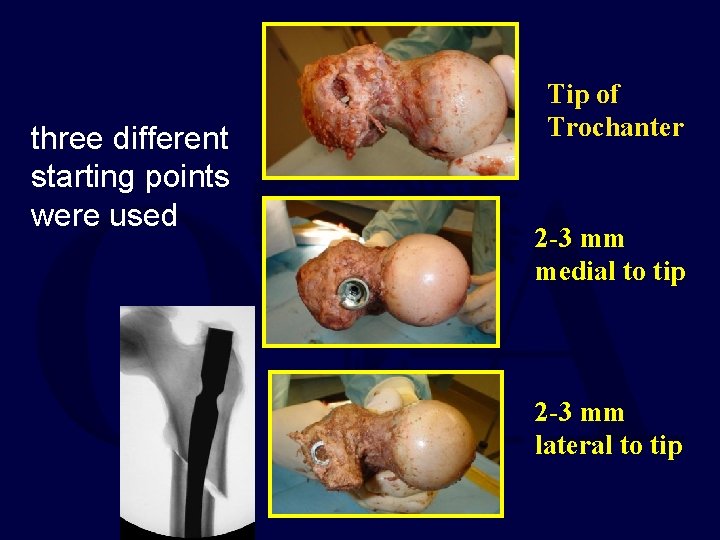

three different starting points were used Tip of Trochanter 2 -3 mm medial to tip 2 -3 mm lateral to tip